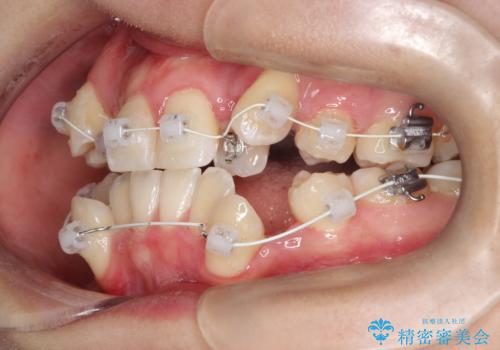

- ワイヤー(審美装置)

- 治療期間

- 2年10ヶ月

- 治療回数

- 30回以上

- 「歯のでこぼこを治したい」を主訴に来院された患者様です。 上下ともに、歯のでこぼこが強く、上下左右4の抜歯をし、ワイヤー矯正で治療を行いました。